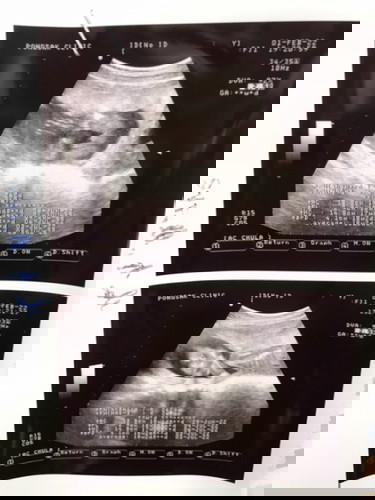

แม่ๆช่วยดูหน่อยค่ะ มีโอกาสที่น้องจะเป็น ญ ไหมค่ะ หมอบอกน้องเป็น ช 80% แงงงง😂😂